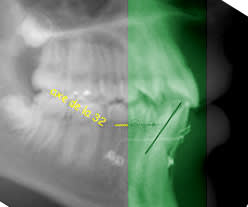

Sur ce cliché, les couronnes sont à autre niveau par rapport à la verticale et pourtant c’est toujours le même cas…

lorsque l'on prend un panoramique le patient se tient debout

la verticale est donc la verticale du patient (a peu de chose pres), le bord des incisives dans la fourchette de de la pano

et non pas tete completement penché en arriere comme tu le simules en faisant une rotation de l'image

car le referentiel c'est la relation de position entre le tube panoramique et la position du patient dans la machine

ainsi le patient est debout et la zone de tomographie est la zone verte comme situé sur mon image (remise dans les conditions reelles de prise du cliché)

par consequent, MOI je dis que la couronne de la canine est situé en arriere de la couronne des incisives mandibulaires ( par rapport à la verticale comme defini precedement) ce que qui fait que la règle enoncé au debut reste juste

et que toi tu dis que la dent est Vestibulaire puisque situé en avant des racines (le contraire étant est assez rare, tu en conviendras)

la regle que j'ai enoncé (et non pas inventée) est complètement dépendante de la technique de prise de cliché orthopantomographique